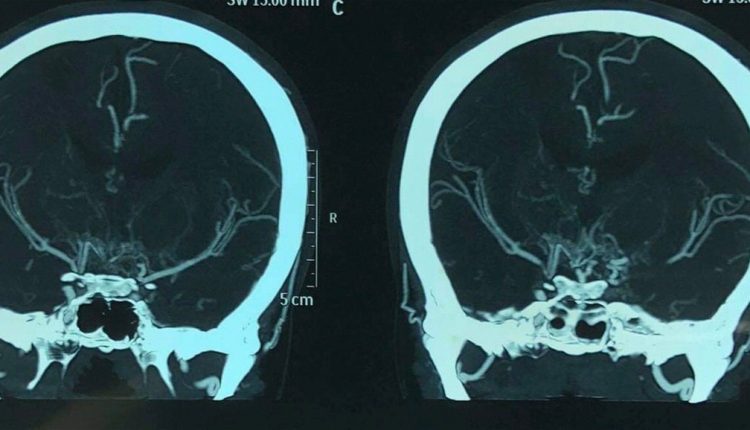

واضاف انه “بعد اجراء الفحوصات السريرية والاشعاعية تبين انها تعاني من قصور شرايين الدماغ الملقب عالميا مرض المويامويا النادر على مستوى العالم”، مبينا انه “تم اجراء عملية من قبل فريق طبي متخصص برئاسة الدكتور سامر العامري وتكللت بالنجاح”.

من جانبه قال رئيس الفريق الطبي الدكتور سامر العامري اخصائي جراحة شرايين الدماغ ان “المريضة ادخلت الى صالة العمليات وتم سحب لها شريان من فروة الراس وزرعه لها ليغذي الدماغ عبر المجهر الجراحي الحديث واستغرقت نحو سبع ساعات وتكللت بالنجاح”.

واوضح العامري ان “العملية تمت عبر تقنية مراقبه الفعاليات العصبية للدماغ المتقدمة وبالاستعانة بالدوبلر الملون بعد تدريب مطول جرى على هذا النوع من العمليات في اليابان”.